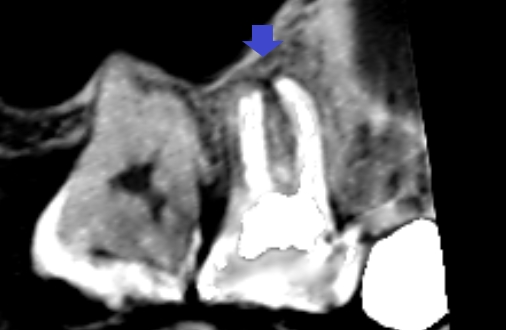

しかし、CTの画像を少しずらしてみると、同じ近心頬側根の中にもう一つの未治療の根管がみられました。青い矢印の先に黒い筋がみられます。これが未治療の根管です。

6カ月後の経過観察時のCT画像です。矢印の先にあった膿の影が消え、歯槽骨が再生しています。